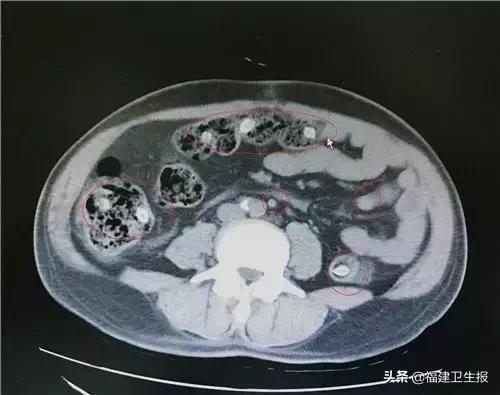

随后,医务人员通过对患者进行盆腔CT检查,结果发现他的肠腔内有10多处核状的异物。